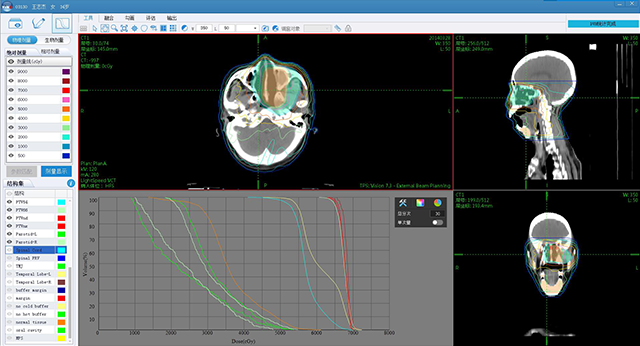

ж”ҫз–—еӯҰ科е»әи®ҫ

иӮҝзҳӨж”ҫз–—дҝЎжҒҜеҢ–дә§е“Ғ

е®үиҜәдә‘жҷәиҝңзЁӢж”ҫз–—еҚҸдҪңе№іеҸ°